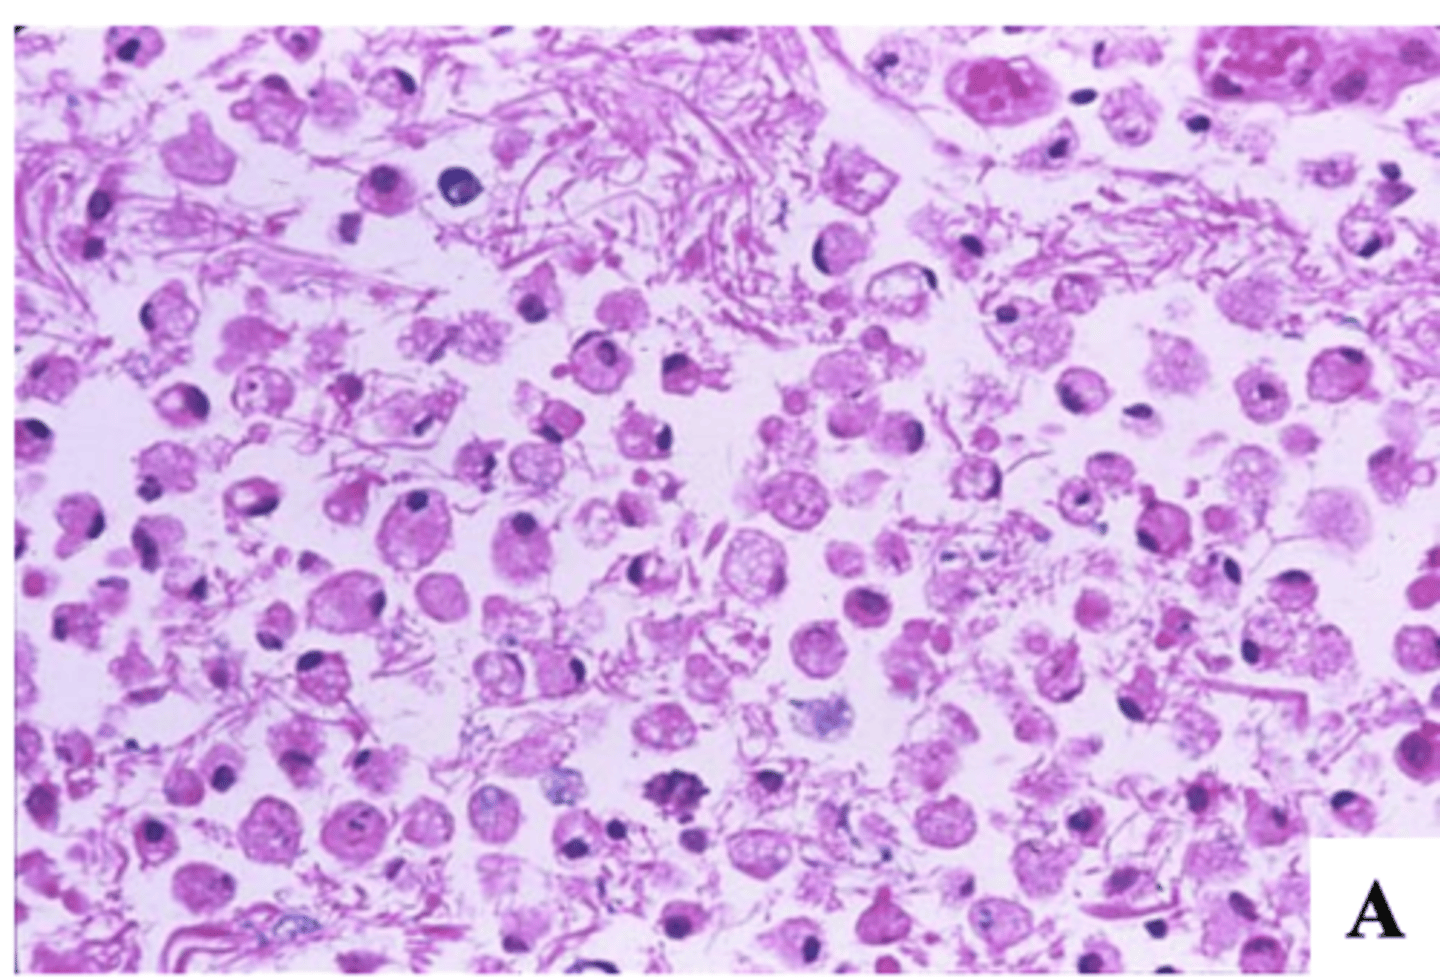

What does the histopathology of an ischemic stroke (infarct) reveal at 6-12 hours after the stroke (acute)?

-red neurons and rarefaction of neuropil (loss/thinning of dense network of axons, dendrites, and glial cell processes in brain's gray matter)

-necrosis

-neutrophils infiltration (12 hours after infarction)

What does the histopathology of an ischemic stroke (infarct) reveal at 1-3 days after the stroke?